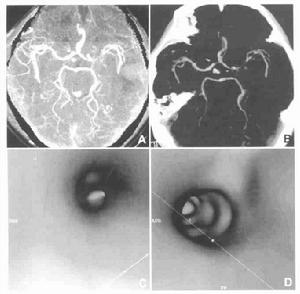

(3)腦血管造影;顳葉腫瘤的頸動脈造影,主要是以血管移位的情況而作腫瘤的定位,顳葉各部腫瘤的血管移位特點如下:

(A)顳葉前部腫瘤

1)前後位像:大腦前動脈縱行段呈直線向對側移位,下部移位較明顯。

2)側位像:大腦前動脈垂直段變直,且向前下方移位。

顳葉腫瘤(B)顳葉中部腫瘤

1)前後位像:大腦前動脈縱行段呈直線狀向對側移位,移位程度不定,有時較輕。

2)側位像:虹吸彎開大,甚至可使床突上段呈直線狀垂直上升。大腦中動脈側裂段中部明顯上移。側裂三角抬高。

(C)顳葉後部腫瘤

1)前後位像:大腦前動脈縱行段呈直線狀向對側移位,有時移位較輕。

2)側拉像:大腦中動脈腦凸面分支(M4、M5)升高,在床頂線上1cm以上,且可呈現弓狀向上突出。

(D)顳葉深部腫瘤

1)前後位像:血管多無明顯變化。

2)側位像:大腦中動脈上移輕微。